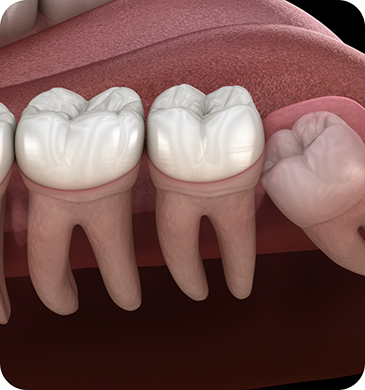

Before we schedule a wisdom tooth extraction procedure for any of our patients, we do a consultation first. During your consultation, we’ll examine diagnostic images of your mouth and speak with you about your symptoms. If we determine that your wisdom teeth need to be removed but they’re still impacted below the gumline, a surgical extraction may be necessary. This involves our team creating a small window in the gumline that will allow us to access the impacted tooth, divide it up into smaller pieces, and remove each of the pieces. However, if the wisdom teeth have erupted, we can complete a simple extraction by lifting them out of their sockets.